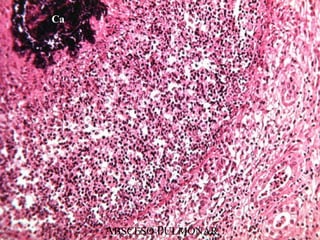

ABSCESO

Ca

3. NECROSIS COLICUATIVA (POR LICUEFACCIÓN)

• Aparece cuando en los tejidos predominan los procesos de

autolisis o heterolisis.

• Típica :

 del SNC

 de las inflamaciones purulentas.

 Otros tipos de necrosis, cuando sufren infección sobreañadida

acaban convirtiéndose en colicuativas.

• Macroscópicamente: masa líquida o semilíquida de material

amorfo que, en los abscesos y flemones, se acompaña de

abundantes leucocitos muertos : pus (líquido más o menos espeso, de

color blanco amarillento o gris verdoso, constituido por serosidades, piocitos

(leucocitos muertos) y leucocitos más o menos alterados con

microorganismos, partículas de grasa y otras substancias fagocitadas).